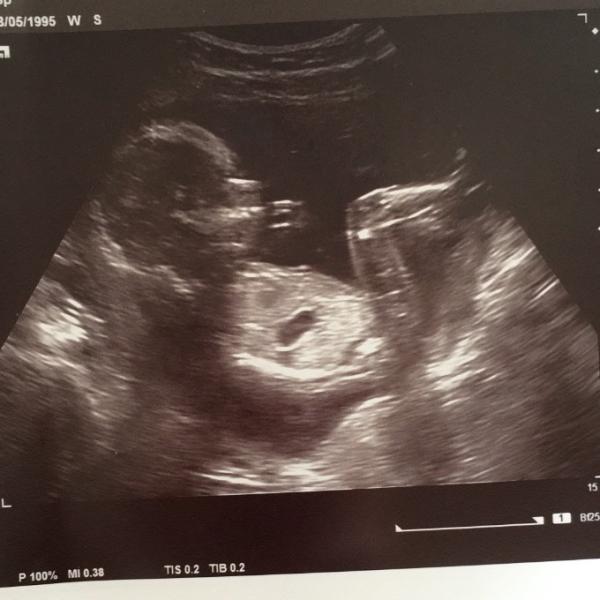

Hallo meine lieben wir sind zurück vom Gyn. Baby gehts sehr gut. Mir solala. Der Frauenarzt hat sehr genau geschaut und hat eine Vermutung geäußert und zwar kriegen wir ein Mädchen, wie ich es erahnt hatte Aber sicher konnte er es nicht sagen es war aber bei 16+4 kein Schniedel zu sehen Mein Freund war Mega stinkig er wollte natürlich einen Bub, aber er kriegt sich wieder ein Anbei ein Bild von der Klee

Bild zu Vorsichtiges Outing - Forum für Januar - Mamis

Hallo So ein schönes Bild! Toll, dass alles ok ist. Hoffentlich freut sich der Papa auch bald über das Mädchen. Vielleicht kriegt ihr noch weitere Kinder, dann wird schon ein Bub dabei sein. LG Edith

Das Bild ja der wahnsinn!!!! Echt toll. Und Mädchen sind klasse. Mein Mann liebt unsere Tochter über alles. So wird es deinem auch gehen

Herzlichen Glückwunsch zum Mädchen Tolles Foto von der Maus